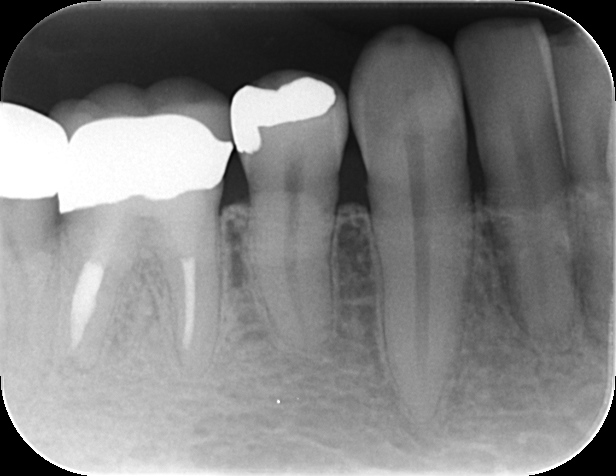

- 10年後の経過:

精密な根管治療を行い、数ヶ月後には骨が再生。10年経った現在も、何でも美味しく噛める状態を維持しています。病変の大きさは、歯の寿命を決める決定打ではありません。